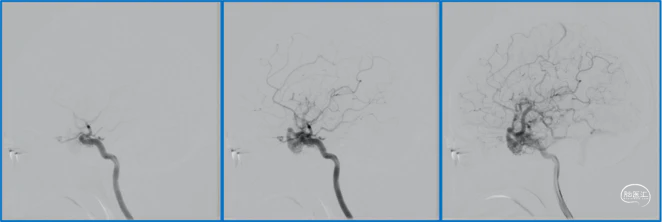

典型病例

蝶顶窦旁DAVF属于Borden III型,需要积极外科治疗。

蝶顶窦旁DAVF,可吸引前和中颅窝硬膜的所有动脉参与供血。其中颈内动脉及其分支的供血可以使用显微外科技术阻断;颈外动脉的供血动脉可以使用介入栓塞技术阻断。

介入栓塞眼动脉供血的要点:超选左侧眼动脉,跃过视网膜中央动脉,栓塞脑膜回返动脉对DAVF的供血。目的:保护眼动脉视网膜中央动脉分支,避免后期栓塞颈外动脉的供血动脉时损伤眼动脉。

引流静脉是否引流进入海绵窦,决定DAVF诊断为“颈动脉-海绵窦动静脉瘘”还是“蝶顶窦旁DAVF”。

静脉的引流路径决定患者静脉高压的临床表现,预后风险,治疗方案。

稳妥的外科治疗方案:先介入栓塞颈外动脉的供血动脉,然后显微手术切断颈内动脉的供血动脉,阻断引流静脉,电凝封闭硬膜瘘口。

神经内镜可以辅助确认颞极深部的引流静脉,避免残留引流静脉。